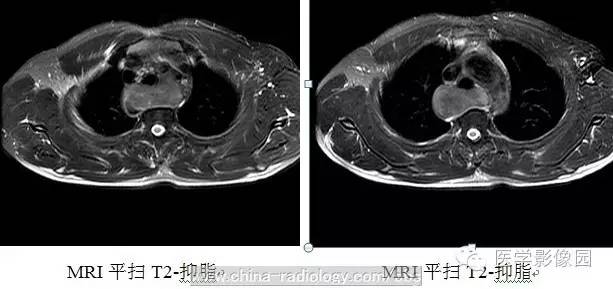

3、CT及磁共振(MRI)检查